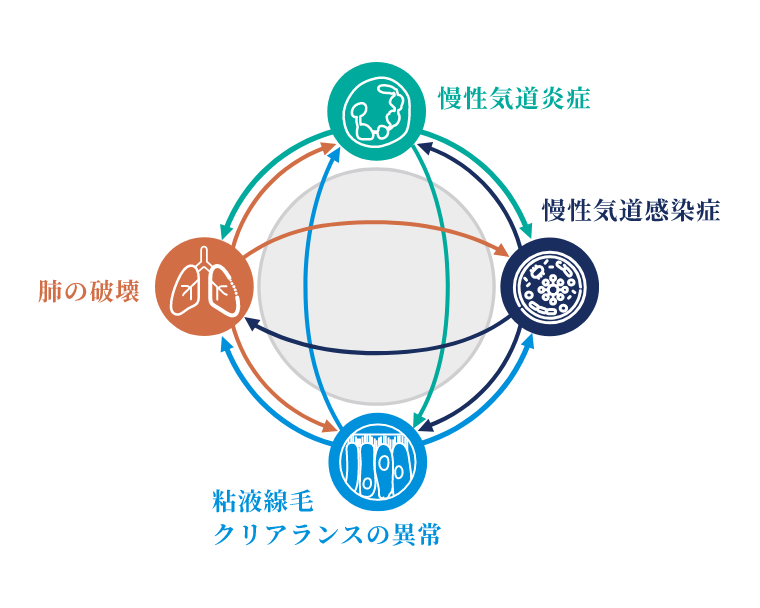

気管支拡張症は、不可逆的に進行する慢性炎症性疾患であり、近年世界的に有病率の増加が示唆され注目が集まっています。

病態